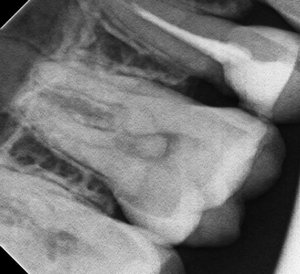

Отвалилась старая пломба, которую ставили девять лет назад. Пришел к стоматологу, она осмотрев сказала, что надо зачистить и заново запломбировать. Начав процедуру чистки, она попробовала пошатать зуб, потом сказала, что нужно сделать снимок. Снимок сделали, ее вердикт — надо удалять зуб, поскольку пошло воспаление вокруг корней, если его лечить со штифтами или еще как, через некоторое время он снова даст о себе знать и все равно придется удалить.